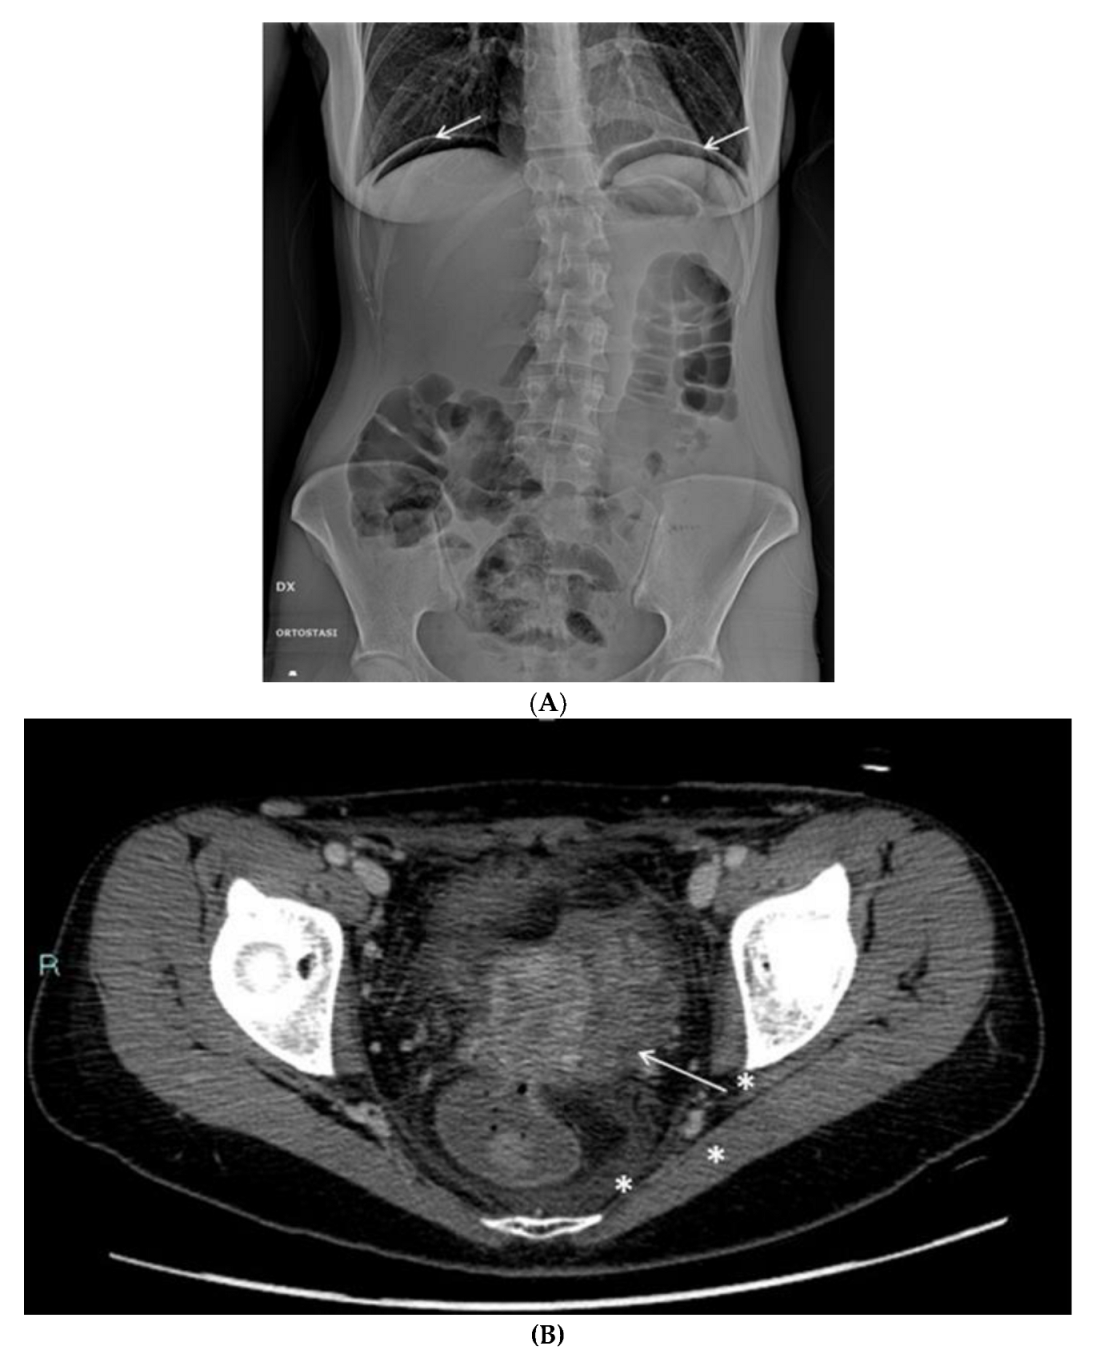

The radiologic tests confirmed the clinical suspicion of vagino-rectal fistula (Figure 7A–C), and the patient underwent adequate surgical treatment.

Figure 7.

(A) Plain radiography shows free subdiaphragmatic air (white arrows). (B) Contrast-enhanced CT. A small fistula (white arrow) connects the rectum with the upper portion of the vaginal canal. Diffuse thickening of soft tissues close to the mesorectal fascia is associated with a thin fluid layer (asterisks). (C) A frame of fluoroscopy obtained through single-contrast enema performed with gastrografin. The contrast medium, injected transvaginally through a small tube (asterisk), spreads into the surrounding soft tissues (white arrows) and, to a lesser amount, into the rectum (arrowhead), confirming the presence of a pervious fistula.